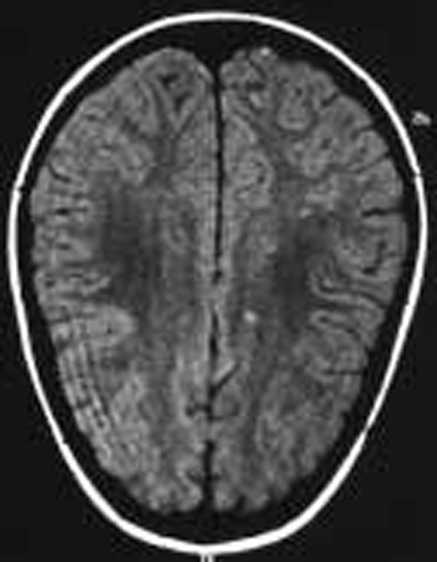

Paciente varón de 11 años de edad sin antecedentes personales de interés remitido desde atención primaria por un cuadro clínico agudo de cefalea y visión borrosa. En el momento de la consulta el paciente se encontraba asintomático. Refería cefalea habitual que en el último mes había aumentado de intensidad y periodicidad, de características pulsátil, localización bitemporal, predominio matutino, que aumentaba con los movimientos de la cabeza y que cedían con analgesia habitual. Se acompañaba de anorexia, pérdida ponderal, labilidad emocional y visión borrosa de manera intermitente. Como antecedentes familiares de interés destacaban numerosos diagnósticos de migraña en la rama materna. La exploración física y neurológica detallada fueron normales. Se le realizó examen de fondo de ojo donde destacaba una discreta palidez de ambas papilas del nervio óptico. Se le practicó una TC, que fue normal, y una punción lumbar que objetivó una presión de apertura de 360 mmH2O, con citoquímica y bioquímica normal. El cultivo y el estudio viral en LCR resultaron estériles. En la RM cerebral se apreciaron pequeñas alteraciones puntiformes de aumento de señal en sustancia blanca subcortical de ambos lóbulos frontales y temporal derecha en densidad protónica y en secuencia T2 (fig. 1). La resonancia por angiografía fue normal. La agudeza visual estaba disminuida (ojo derecho, 0,7, y ojo izquierdo, 0,8) y en la campimetría se apreciaba una pérdida visual bilateral (ojo izquierdo 14/120; ojo derecho 22/120). Los potenciales visuales evocados manifestaban retraso de latencia en la vía óptica, sobre todo izquierda. El estudio de autoinmunidad fue normal. El estudio de hipercoagulabilidad reflejó un estado de heterocigosis para el factor V de Leiden con una resistencia para la proteína C (ratio): 1,87 (normal: 2-5). El estudio familiar desveló el estado de heterocigosis del padre con una resistencia a la proteína C (ratio): 1,65 (normal: 2-5).

Figura 1.Caso 1. Lesiones hiperintensas puntiformes sugerentes de microinfartos.